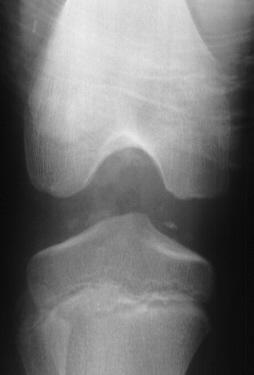

RADIOGRAPHS:

AP, lateral and obliques of the left knee showed an effusion with multiple radiodense bodies that were felt to be intraartictilar . No fractures or dislocations were evident. Comparison views of the right knee were unremarkable.